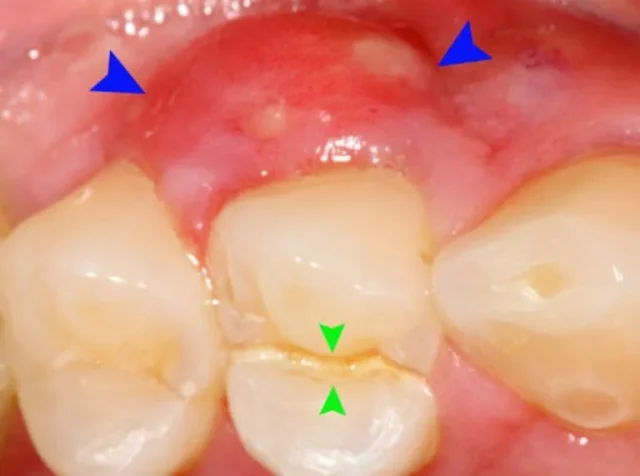

Sưng nướu răng, còn được gọi là viêm nướu, là tình trạng mô nướu (lợi) xung quanh răng bị viêm nhiễm, sưng phồng, đỏ tấy và thường dễ chảy máu. Tình trạng này xảy ra khi các vi khuẩn có hại tích tụ trong các mảng bám và cao răng không được loại bỏ hiệu quả qua quá trình vệ sinh răng miệng hàng ngày. Mảng bám vi khuẩn này tạo ra độc tố, gây kích ứng và viêm nhiễm mô nướu, khiến vùng lợi trở nên nhạy cảm và dễ tổn thương.

- Nướu bị sưng đỏ: Đây là dấu hiệu dễ nhận thấy nhất. Thay vì có màu hồng nhạt khỏe mạnh, nướu chuyển sang màu đỏ tươi hoặc đỏ sẫm, trông có vẻ căng phồng.

- Xuất hiện mủ: Trong những trường hợp viêm nhiễm nặng hơn, bạn có thể thấy có mủ chảy ra từ khe nướu hoặc một cục mủ hình thành trên nướu. Đây là dấu hiệu của áp xe nha chu và cần được điều trị khẩn cấp.

- Nướu sưng kèm mủ: Đây là dấu hiệu của nhiễm trùng nặng hơn, có thể là áp xe nha chu hoặc áp xe quanh thân răng. Tình trạng này không thể tự hết mà cần được thăm khám và điều trị kịp thời bởi nha sĩ. Nếu không, nhiễm trùng có thể lan rộng, gây tổn thương xương và các răng xung quanh.